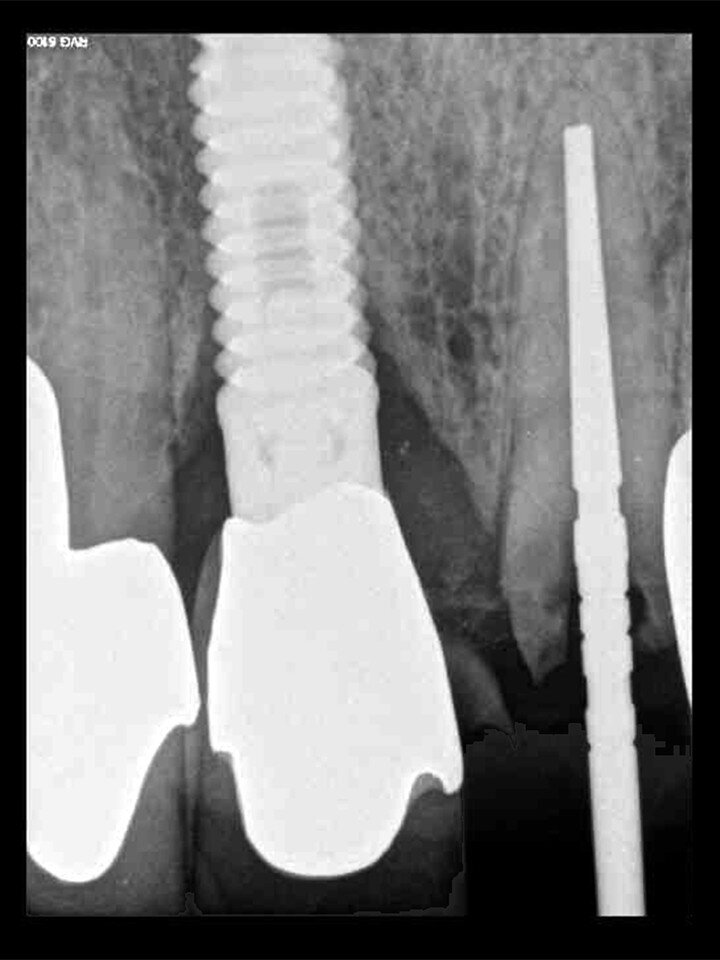

Fig. 13: The pre-op periapical radiograph revealed an existing implant-supported metal–ceramic restoration for the adjacent region #11.

Fig. 18: A periapical radiograph

with a drill in place confirmed that the apex length had been reached and that all the gutta-percha had been removed.

A 62-year-old male patient presented with a hopeless prognosis for a post fracture in the left central incisor requiring extraction (Figs. 12a & b). The preoperative periapical radiograph revealed an existing implant supporting a metal–ceramic restoration for the adjacent region #11 (Fig. 13). The CBCT (CS 9600, Carestream Dental) cross-sectional image revealed a favourable preoperative condition relating to the trajectory of the endodontically treated root to the alveolus for a PET procedure (Fig. 14a). Using the native Carestream 3D Imaging software, a simulated implant and abutment projection was positioned within the available bone to avoid the root fragment (Fig. 14b).